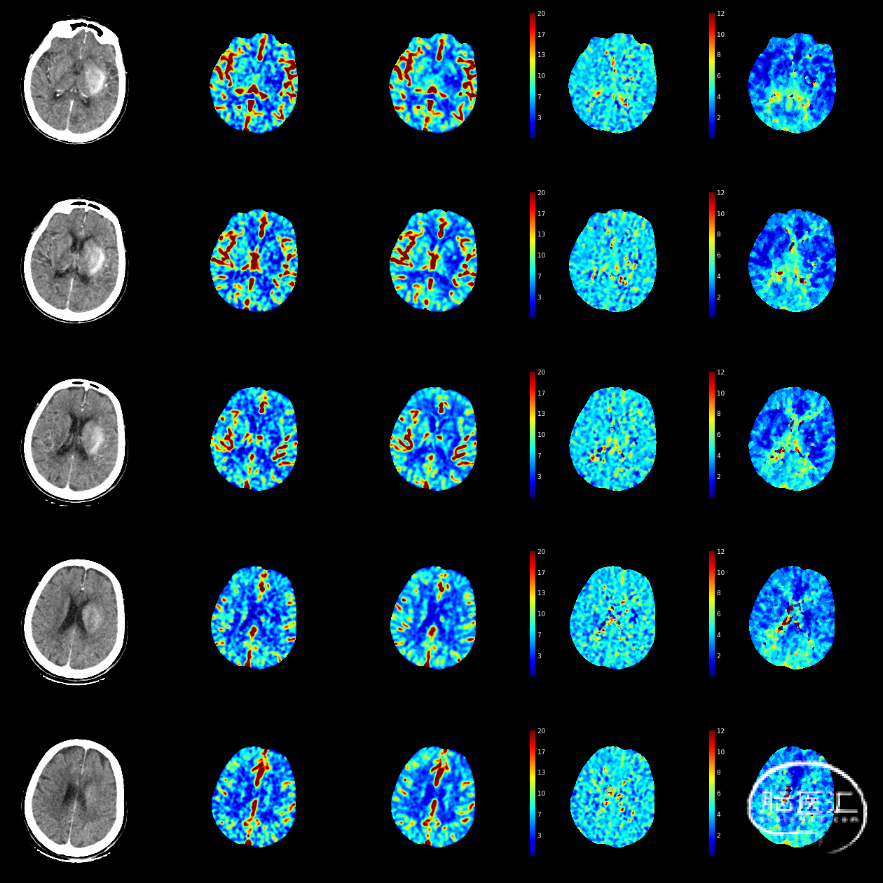

CTP

多模式影像学评估可协助血管闭塞性质的判断,特别是多时相CTA扫描;